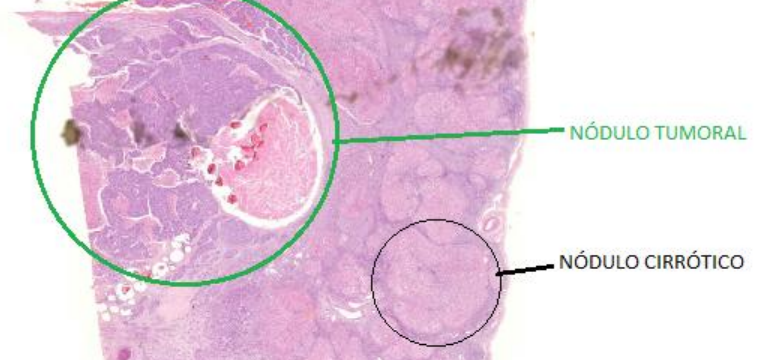

Carcinoma hepatocelular moderadamente diferenciado com cirrose (A539)

Nódulo tumoral

Mais basofílico (mais azul)

Nódulo cirrótico

Mais claro

Desmoplasia